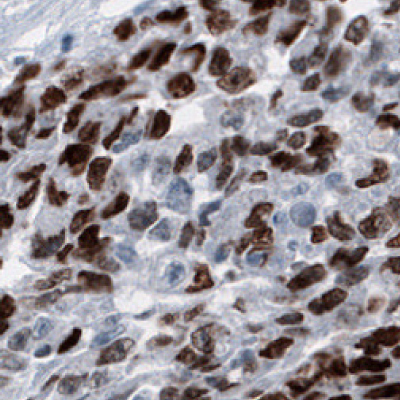

SALL4

Targeting GSCs is an extremely important aspect of the clinical treatment of gliomas. A better comprehension of glioma GSCs provides functional insights into the dynamics of cellular communication during glioma genesis, creating new opportunities for diagnostics and therapeutics.

The transcription factor SALL4 participates in cell proliferation, apoptosis, cycle, invasion, evolution, and drug resistance. SALL4 is overexpressed in glioma and correlated with poor outcomes.21 SALL4 acts by strengthening the PI3K/AKT signaling pathway (which is a well-known pathway in the regulation of tumorigenesis, significantly activated in glioma) thus reducing the expression of the tumor suppressor PTEN (Liu 2017).22

Figure 6 shows the characterization of SALL4 in human and mouse tissues and Figure 7 shows an example of SALL4 upregulation in glioma samples.

Figure 6A.Immunohistochemical staining using the Anti-SALL4 monoclonal antibody showing nuclear positivity in germinal cells in testis.

Figure 6B.Immunohistochemical staining using the Anti-SALL4 monoclonal antibody showing nuclear positivity in germinal cells in an oocyte.

Figure 6C.Immunohistochemical staining using the Anti-SALL4 monoclonal antibody showing nuclear positivity in germinal cells in embryonal testis carcinoma human tissues.

Figure 6D.Immunohistochemical staining using the Anti-SALL4 monoclonal antibody showing nuclear positivity in a subset of cells in the developing brain in mouse embryo E11.

Figure 7A.Multiplexed IHC-IF staining of human normal cortex samples using the Anti-SALL4 monoclonal (nuclear, in red) and the Anti-PTEN monoclonal (cytoplasmic, in green) antibodies. Nuclei are counterstained with DAPI (in blue).

Figure 7B.SALL4 is upregulated in glioma samples compared to Figure 7A. Multiplexed IHC-IF staining of glioblastoma samples using the Anti-SALL4 monoclonal (nuclear, in red) and the Anti-PTEN monoclonal (cytoplasmic, in green) antibodies. Nuclei are counterstained with DAPI (in blue).